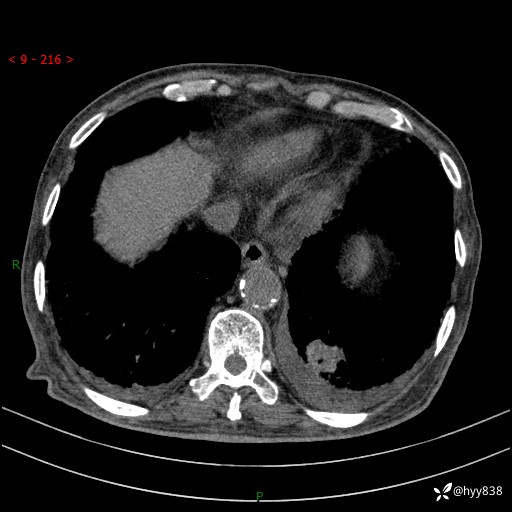

老年男性,间断咳嗽咳痰20余年,加重伴发热1天。呼吸科疑难病例讨论---结果公布

主诉:间断咳嗽咳痰20余年,加重伴发热1天

简要病史:家属代诉患者于20余年前无明显诱因出现咳嗽咳痰,痰为白色泡沫状,未行特殊治疗,不伴胸痛、胸闷、气喘、咳血等不适,1天前上午患者无明显出现发热,查体温39℃,伴咳嗽,咳痰无力,自行予以物理降温对症治疗,今晨2点左右再次出现发热,体温达40℃,自行服用复方氨酚烷胺对症治疗,凌晨3点左右复测体温38.2℃,现患者为求进一步诊治于今日就诊于我院门诊,行胸部CT提示双肺感染,遂以“肺部感染”收入我科。 患者本次起病来精神、食欲、睡眠欠佳,体力下降,体重无明显变化。

辅助检查:CT

胸部CT平扫